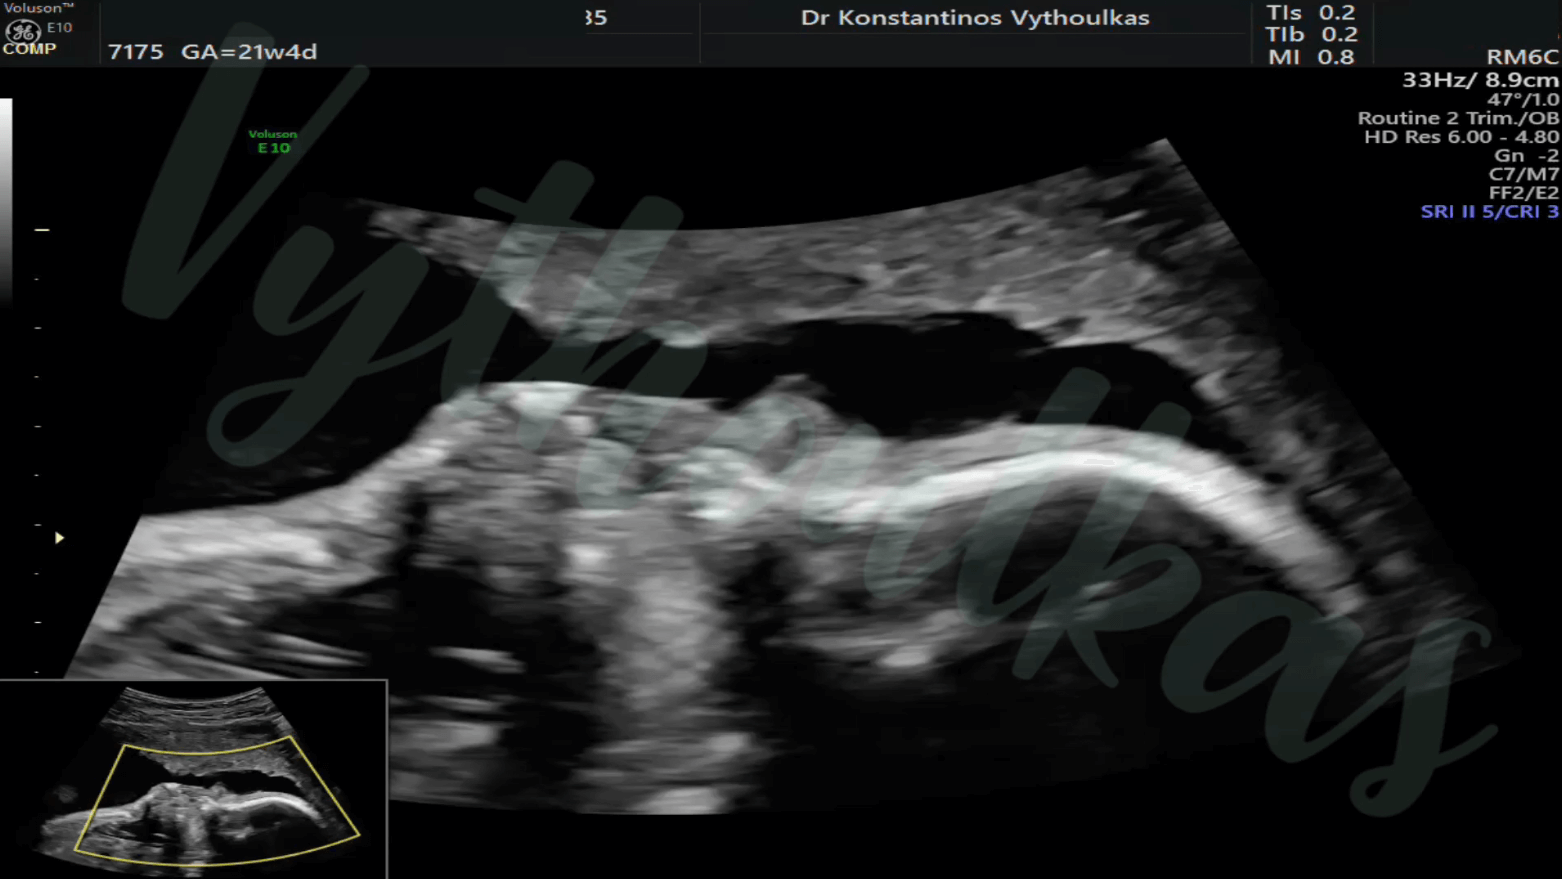

- Υπερηχογραφική εξέταση, η οποία συμβάλλει στη διαπίστωση της ενδομήτριας κύησης και αποκλεισμό της έκτοπης κύησης. Επιπλέον, μπορεί να διαπιστώσει εάν πρόκειται για μονήρη ή πολύδυμη κύηση, να ανιχνεύσει την εμβρυϊκή καρδιακή λειτουργία μετά τις 6 εβδομάδες και να προσδιορίσει υπερηχογραφικά την ηλικία κύησης, με βάση το κεφαλουραίο μήκος του εμβρύου μετά τις 8 εβδομάδες.